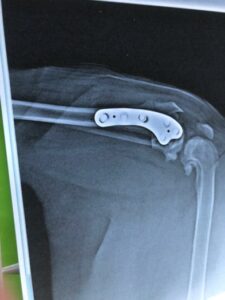

Joelle: « Maï Lin a subi aujourd’hui une opération des ligaments croisés; c’est pour ça qu’elle avait du mal à marcher, enfin espérons que ça ira mieux après. »

28 mai: 15 jours après l’opération Maï Lin va bien, mais Joëlle a eu une très grosse frayeur, et nous aussi:

De retour de l’opération des ligaments croisés Maï Lin n’était pas très en forme et bien sûr Joëlle a mis ça sur le compte de l’anesthésie.

Malheureusement le lendemain c’était pis et Joëlle a tout de suite pensé à une dilatation ou torsion d’estomac car qui a connu ça ne peut plus jamais passer à côté…

Maï Lin a été prise en charge tout de suite et a eu beaucoup de chance de s’en remettre ca non seulement l’estomac était retourné mais aussi la rate.Bien sûr le vétérinaire a été très performant, mais on peut dire aussi que Maï Lin est dotée d’une belle force vitale.

Profitant de cette seconde anesthésie le veto a aussi opéré le voile du palais….

Une fois de plus on ne peut que mettre en garde sur le post op: l’acte chirurgical pose rarement problème et l’anesthésie non plus. Sur le nombre de chows que nous suivons, près de 600, nous n’avons eu qu’à déplorer le décès d’un loulou au cours de l’anesthésie, celui du regretté Murphy. Mais ce qui est très souvent problématique c’est la garde en cage jusqu’au réveil. Privilégiez les vétérinaires qui vous rendront le chow très vite après l’opération, c’est avec vous, en confiance, que votre chien ne stressera pas et évitera coup de chaleur et dilatation d’estomac.